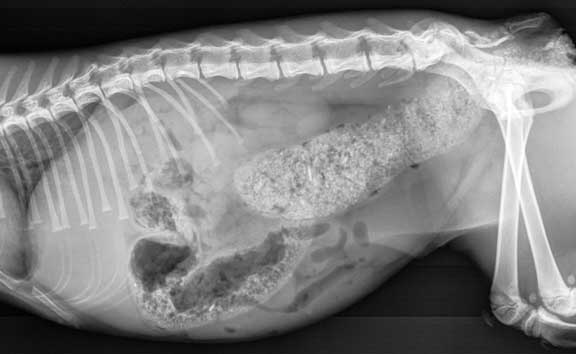

The thorax

W- windpipe (trachea)

H- heart

VC- vena cava

Sto- stomach

This view is towards the front of the abdomen

L- Liver

S- Stomach (filled with food)

K- Kidneys (they are overlapping)

LI- Large intestine (filled with stool)

SI- Small Intestine

Sp- Spleen